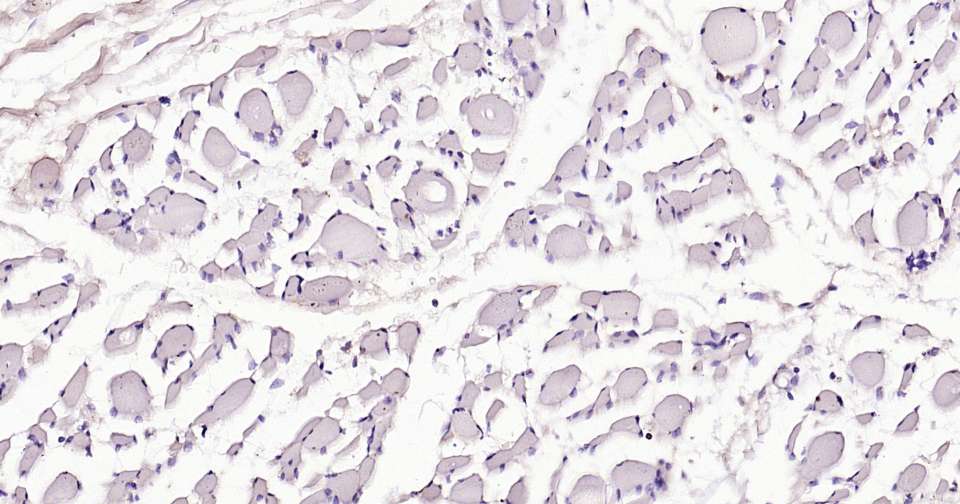

Immunohistochemical analysis of paraffin embedded human skeletal muscle tissue slide using IHC0397H (Human CD11c IHC Kit).